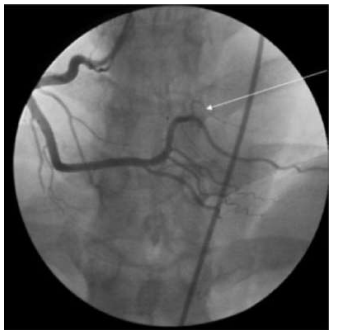

Qual é a artéria assinalada na seguinte figura, considerando essa incidência oblíqua anterior esquerda?